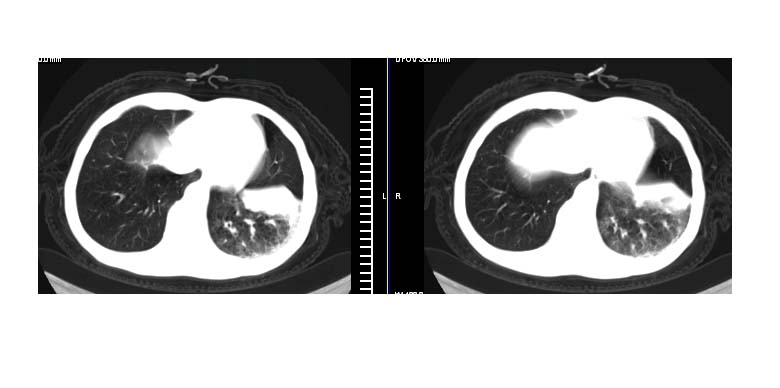

标题: CT11019:男性,66岁。发烧5-6天。治疗后无明显好转。 [打印本页]

标题: CT11019:男性,66岁。发烧5-6天。治疗后无明显好转。

左肺门下分增大见有结节影,基底干及分支显示不清,下叶体积缩小,呈片带状机磨玻璃样影显示。支持考虑左下肺中心型肺癌伴阻塞性肺炎及部分肺不张。建议纤支镜检查

先做增强扫描,然后建议支纤镜活检或ct引导下穿刺活检,

明明是斜裂胸膜积液,为何都考虑阻塞性肺炎、肺不张(边缘内凹,而本例是外凸)。

以下是引用拾荒者在2007-12-24 19:47:00的发言:[br]明明是斜裂胸膜积液,为何都考虑阻塞性肺炎、肺不张(边缘内凹,而本例是外凸)。